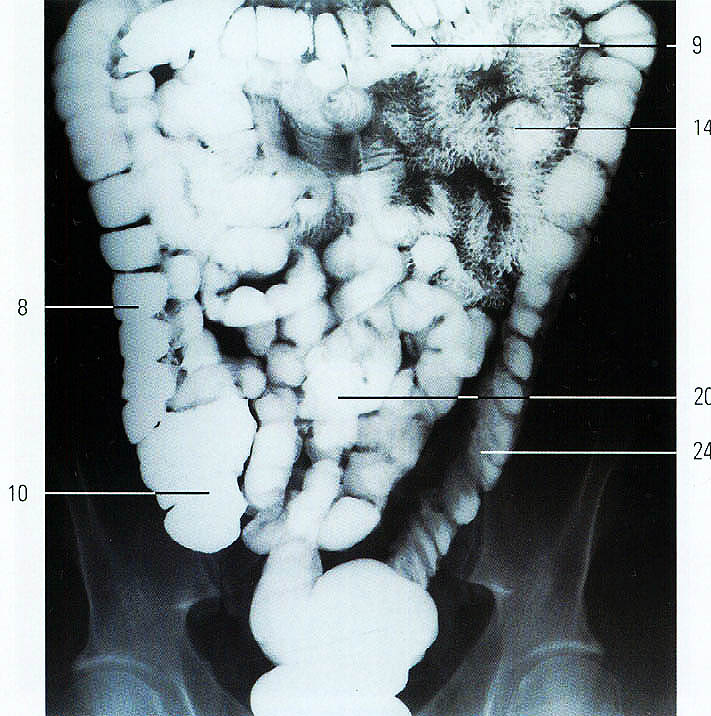

Рентгеноконтрастные Исследования Кишечника: Визуализация и Методики

Раздел: Иллюстрированный журнал